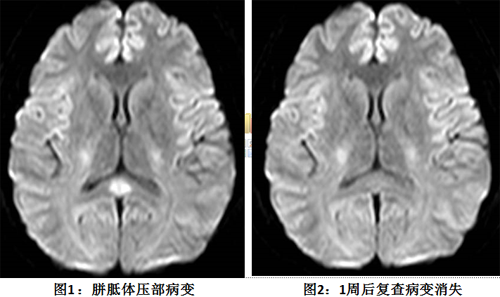

患者于当晚完成了头颅磁共振检查,果然在胼胝体压部见到了异常高信号(在T2、FLAIR、DWI等序列,胼胝体压部显示卵圆形高信号),随后的病原学检查也显示乙型流感病毒抗体IgM阳性。自此,RESLES诊断明确。经过抗病毒、脱水降颅压、营养神经、激素等综合治疗后,患者头痛迅速缓解,间隔8天后复查脑MRI胼胝体压部高信号消失,复查腰穿颅压恢复正常,脑脊液细胞数基本正常,右眼球活动也逐渐恢复,复视消失。

可逆性胼胝体压部病变综合征(RESLES)临床少见,是一种由多种病因引起、胼胝体压部存在特征性影像学表现的临床及影像学综合征。病因包括了感染、代谢紊乱、抗癫痫药物应用等,其中感染常见于儿童、青少年,病原体以病毒为主,最常见为流感病毒,其他包括轮状病毒、麻疹病毒、6型疱疹病毒等。影像学特点是颅脑MRI上胼胝体压部(SCC)的卵圆形、非强化高信号病灶。病灶一段时间后可完全消失,故有时不一定能捕捉到。积极治疗后大多预后良好,可不遗留神经功能障碍。